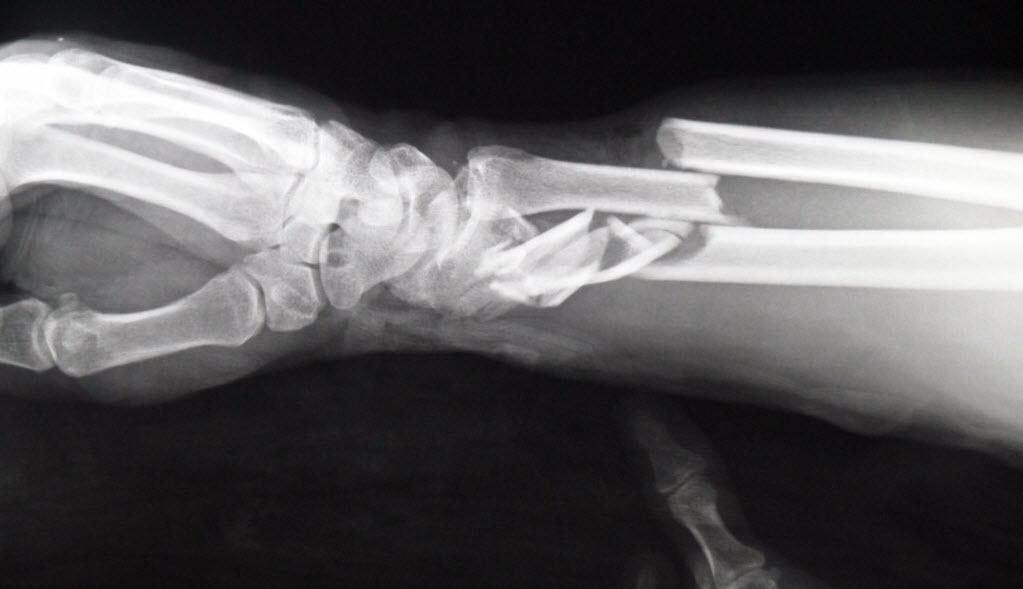

Untuk mendiagnosis patah di tangan, dokter akan menanyakan bagaimana cedera terjadi serta apa saja gejala yang Anda rasakan. Kemudian, dokter akan melakukan pemeriksaan fisik untuk melihat tanda-tanda fraktur di area tangan, lengan, atau siku Anda.

Bila dicurigai mengalami patah tulang, dokter akan meminta Anda untuk melakukan tes pencitraan guna memastikan diagnosisnya. Beberapa tes pencitraan tersebut, yaitu:

- Sinar-X, untuk memperoleh gambar struktur tulang dan mengidentifikasi tulang yang patah.

- Tes CT scan, untuk mengidentifikasi cedera pada jaringan lunak dan pembuluh darah di sekitar tulang yang tidak dapat diperoleh oleh sinar-X.

- Tes Magnetic resonance imaging (MRI), untuk menghasilkan gambar rinci tulang dan jaringan lunak, yang tidak didapat oleh sinar-X.